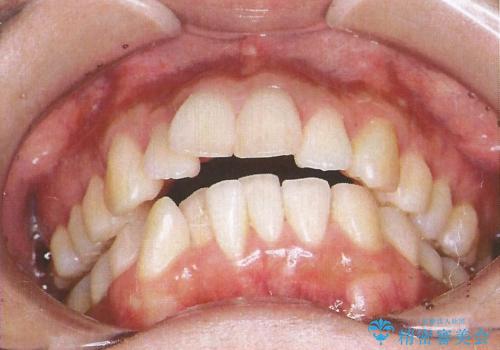

- 出っ歯を目立たない器具で治療したいとのことで来院されました。

上顎の前から4番目の歯を両側抜歯して、上下裏側の装置で前歯を引っ込める計画としました。